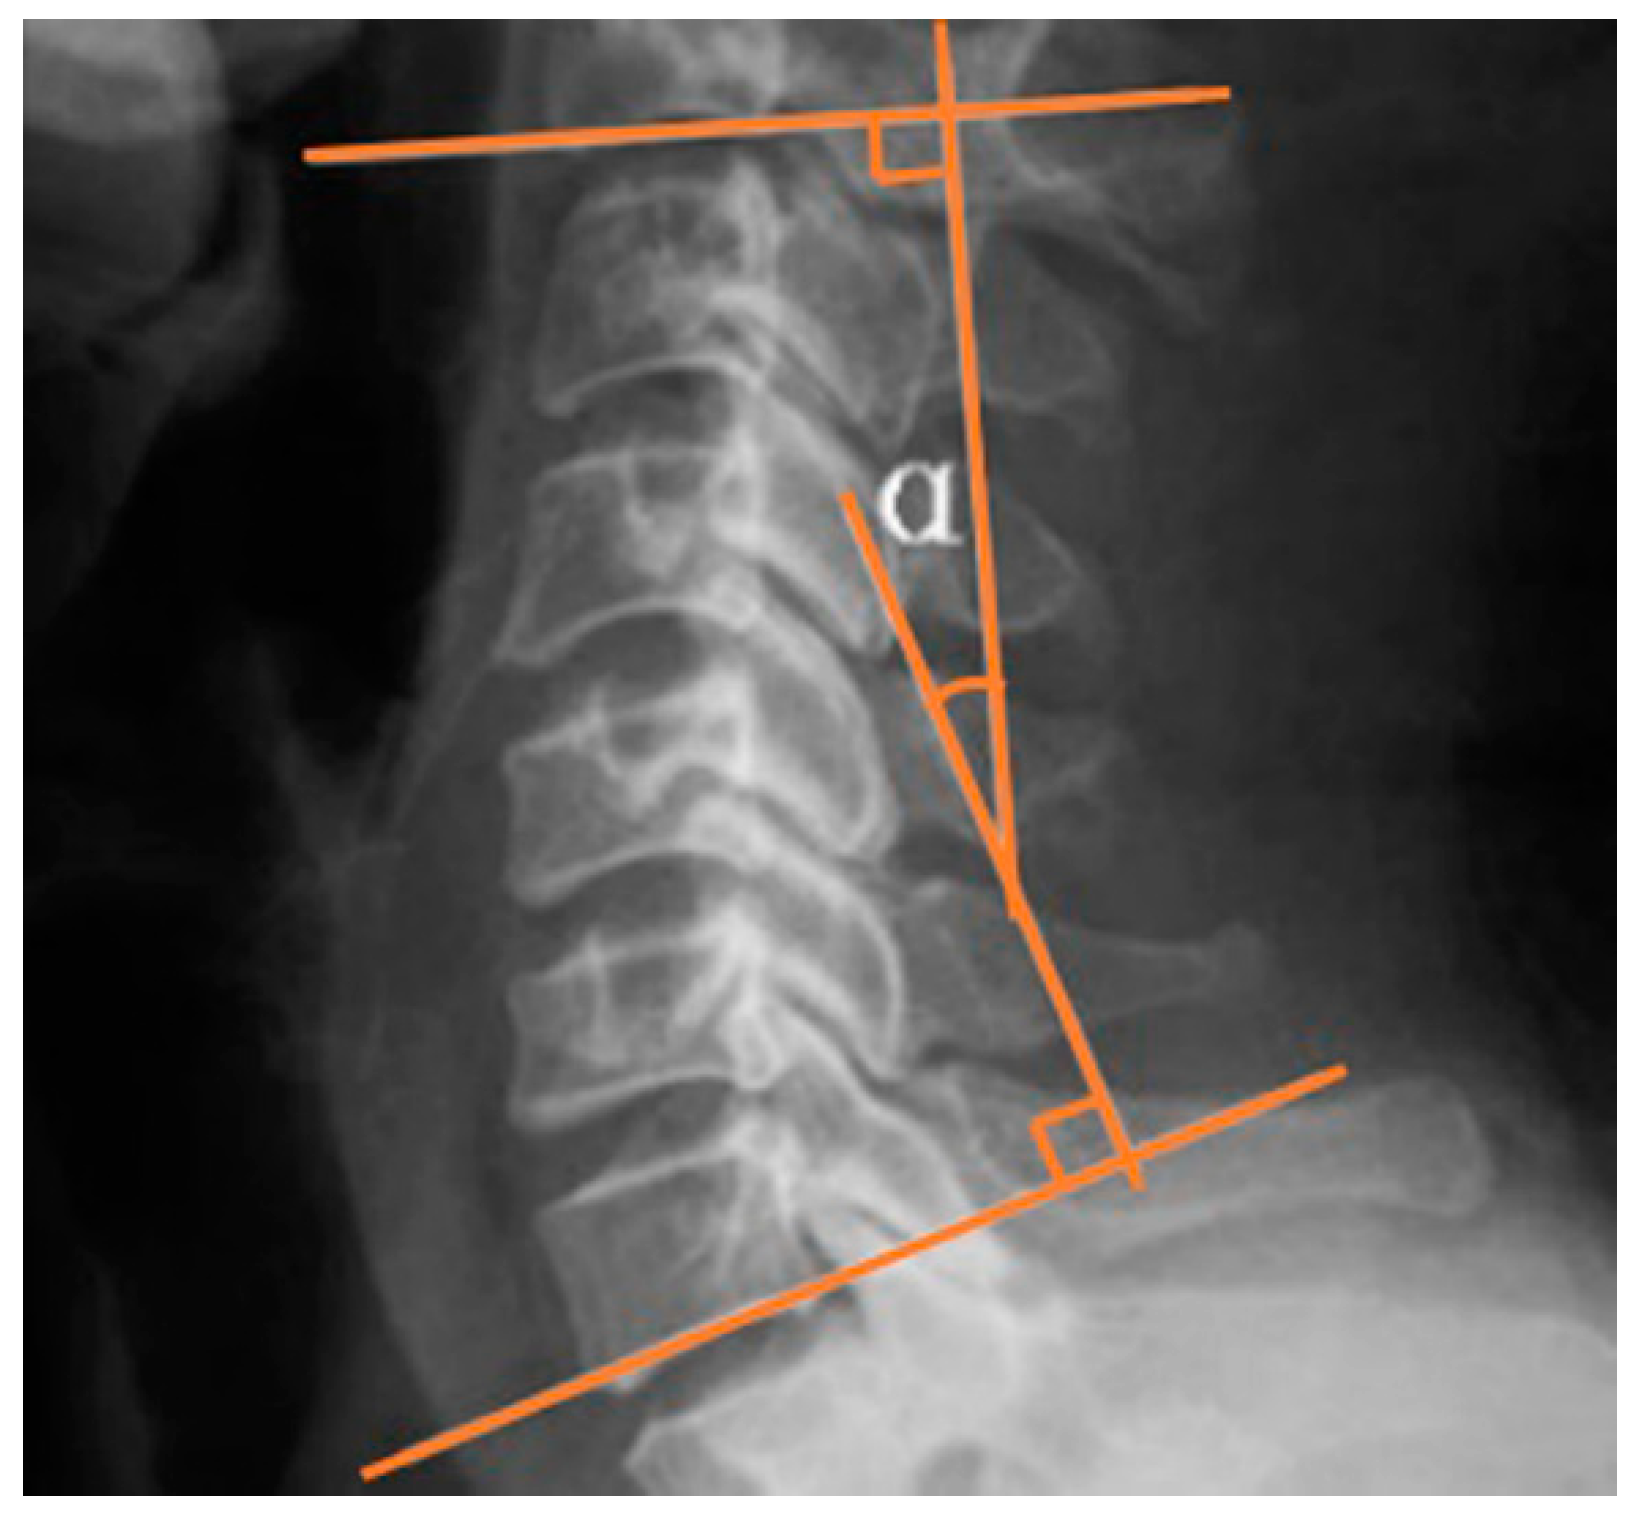

As shown in Figure 2, the Cobb angle was calculated by measuring the angle between the superior border of the C2 vertebral body and the inferior border of the C7 in neutral position in lateral view of cervical spine X-ray.

Figure 2.

Cobb angle of cervical lordotic curve.

The morphological changes after treatment are shown in Table 3. The Cobb angle of the C-LCCT group at C2–7 was significantly increased after treatment (4.8° ± 10.9 and 16.9° ± 12.7, before and after treatment, respectively). Conversely, the TT group showed no significant difference in the Cobb angle after treatment at C2–7(5.2° ± 8.6, 4.9° ± 9.8). Rather, cervical lordosis was decreased slightly.